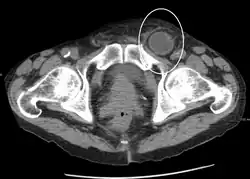

Hérnia inguinal encarcerada, como visto na TC

No diagnóstico de hérnias abdominais, a imagem é o principal meio de detectar hérnias diafragmáticas internas e outras hérnias não palpáveis ou não suspeitas. A tomografia computadorizada com múltiplos detectores (TCMD) pode mostrar com precisão o local anatômico do saco de hérnia, o conteúdo do saco e quaisquer complicações. A TCMD também oferece detalhes claros da parede abdominal, permitindo que as hérnias sejam identificadas com precisão.[9]

De longe, as hérnias mais comuns (até 75% de todas as hérnias abdominais) são as chamadas hérnias inguinais. As hérnias inguinais são ainda divididas na hérnia inguinal indireta mais comum (2/3, representada aqui), na qual o canal inguinal é inserido através de uma fraqueza congênita em sua entrada (o anel inguinal interno) e o tipo de hérnia inguinal direta (1/3), onde o conteúdo da hérnia passa por um ponto fraco na parede traseira do canal inguinal. As hérnias inguinais são o tipo mais comum de hérnia em homens e mulheres. Em alguns casos selecionados, eles podem exigir cirurgia. Há casos especiais em que a hérnia pode conter hérnia direta e indireta simultaneamente hérnia pantalonariana, ou, embora muito rara, pode conter hérnias indiretas simultâneas.[15]